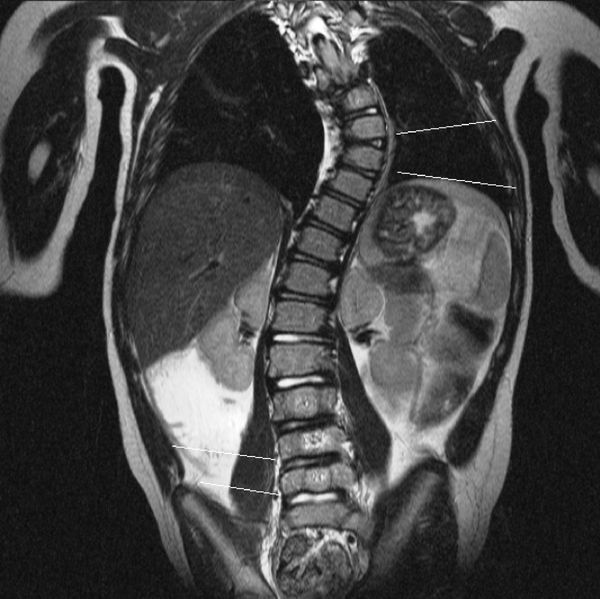

При изучении МРТ снимков возможно:

- оценить состояние межпозвонковых дисков и степень их дегенерации;

- выявить протрузии — выпячивания диска без разрыва фиброзного кольца;

- выявить гемангиомы тел позвонков — доброкачественные сосудистые опухоли;

- оценить степень выраженности стеноза позвоночного канала и состояние межпозвонковых отверстий и т. д.

![Сколиоз на МРТ [34] Сколиоз на МРТ [34]](/media/bolezny/narusheniya-osanki/skolioz-na-mrt-34_s.jpeg?dummy=1770634323978)

Сколиоз на МРТ [34]